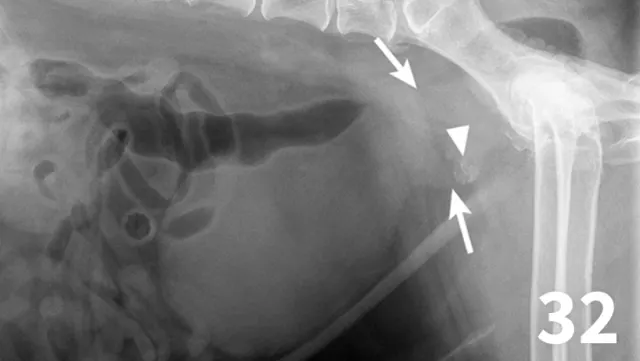

Survey radiography can be used to evaluate the size, shape, and opacity of the prostate gland (Figures 31 and 32). Ultrasonography has the advantage of providing tissue-architecture information. Prostatic abscesses, internal cysts, and paraprostatic cysts are readily visualized on ultrasonography. Ultrasonography can also aid in diagnosing benign hyperplasia (homogenous echotexture with intact capsule) and prostatic neoplasia (heterogenous with course echotexture and irregular margins) (Figure 33) and with identifying any potential source of excess androgen production (eg, adrenal glands, retained testes) in cases of suspected squamous metaplasia of the prostate gland. Mineralization of the prostate in a neutered dog is suggestive of neoplasia and can be detected by both survey radiography and ultrasonography. Sublumbar lymph nodes can also be evaluated by ultrasonography, whereas radiography is best for evaluating the adjacent lumbar spine (Figures 34 and 35).

Figure 31.

The prostate gland (arrows) in this intact male dog is enlarged but normal in shape with smooth margins and soft tissue opacity. Although this is consistent with benign prostatic hypertrophy, ultrasound would be useful to further define tissue architecture.